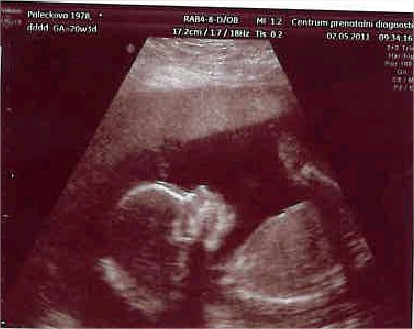

Ahoj holky, tak jsem zpet z Londyna.. ja tam taaak nakupovalaaaa.. maji to tam uzasne levne.. tak treba kozene boticky Nike za 13 GBP = cca 360 Kc, atd. atd.. bodycka v krasne kvalite vyjdou na 40Kc a to jsem nekupovala ty nejlevnejsi.. trosku uz jsem myslela dopredu a kupovala velikosti 6-12, protoze 0-6 uz mame doma od kamaradky. Nase mala bude s nami v loznici, protoze mame jen 2+kk, takze pokojicek bohuzel jeste resit nemuzeme. Ale po materske si poridime neco vetsiho.. Jinak diky za tipy na Globus, taky ted potrebuji koupit perinky a povleceni, tak se tam rozjedu. A take prikladam posledni snimek Kacenky..